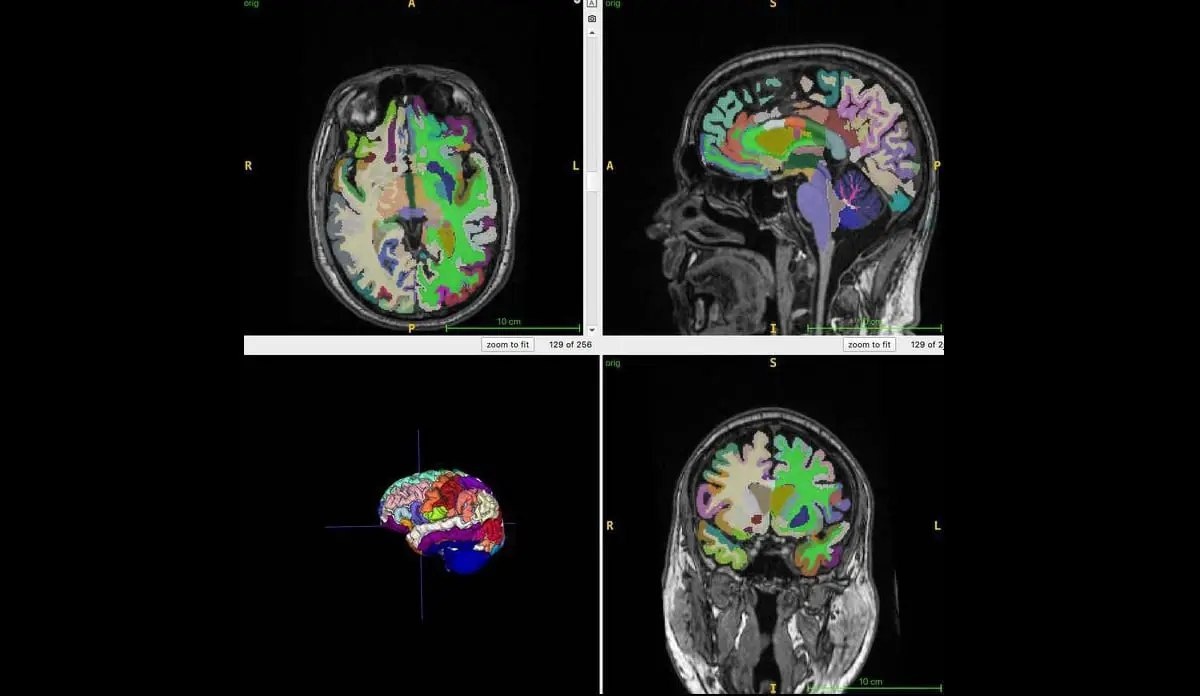

Искусственный интеллект подтверждает, что мышечная масса замедляет старение мозга

Прикинь, наука реально подтвердила: больше мышц и меньше живота — и мозг моложе! ИИ даже помог это доказать, покопавшись в данных кучи народу. Так что качай железо и гоняй висцеральный жирок, чтобы мозг оставался на волне, неважно, сколько тебе по паспорту!